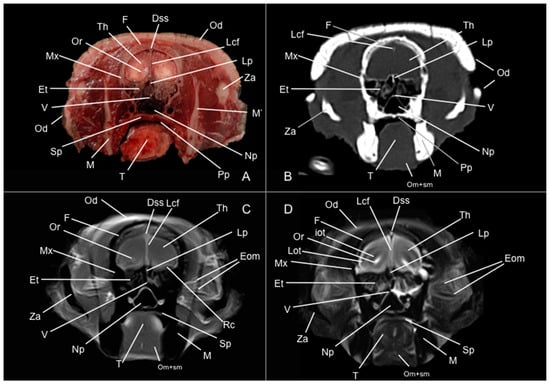

3. Results

3.1. Anatomical Study

3.2. Computed Tomography Study

3.3. Magnetic Resonance Imaging (MRI)